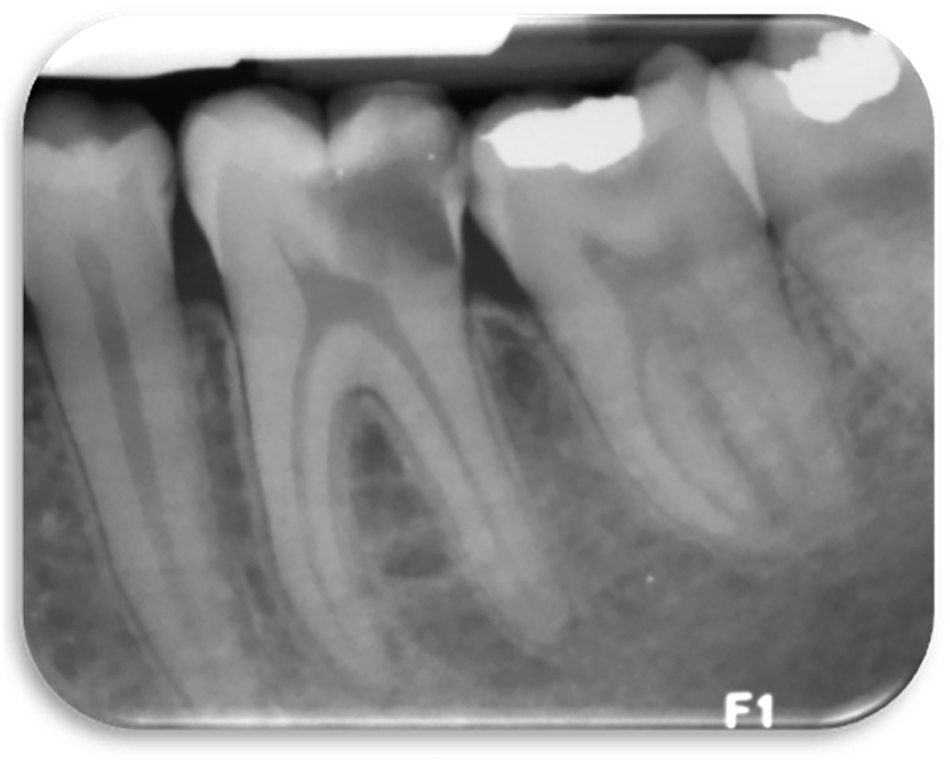

Periapical radiograph of lower left quadrant.